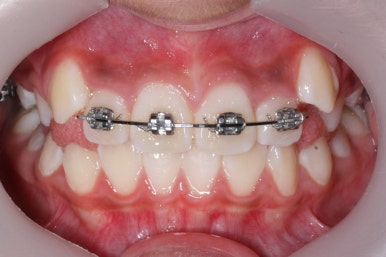

초진 시의 모습입니다.

11살의 어린이였기에 몇 군데 아직 유치가 남아있었습니다. 영구치가 모두 나오지 않았죠. 덧니가 있고 치열이 고르지 못하더라도 일반적으로 영구치가 더 나온 후에 연산동덧니교정 하는 것을 권해드립니다.

첫 장치 부착한 모습입니다.

아직 유치가 몇 개 남아있기에 장치가 전체적으로 부착되지 않습니다. 우선 앞니 4개만 먼저 치열을 맞추고 위쪽 어금니는 후방 이동을 해주면서 교합을 맞추며 덧니가 내려올 공간을 확보합니다.

연산동덧니교정 키다리아저씨치과에서는 메탈 장치를 사용했습니다.

많이 사용 되는 클리피씨 장치 등의 세라믹 보다는 아이가 양치하기 쉬운 부피가 작고 비용도 덤으로 낮은 메탈장치를 사용했습니다.